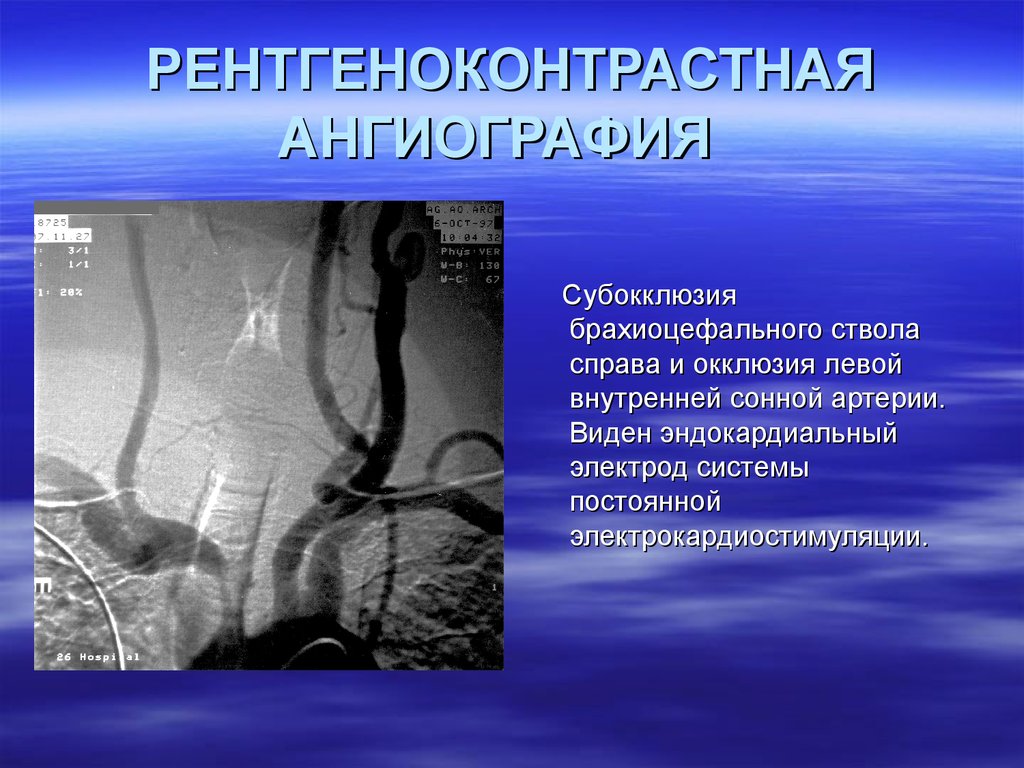

Хроническая окклюзия артерий: причины, симптомы и лечение